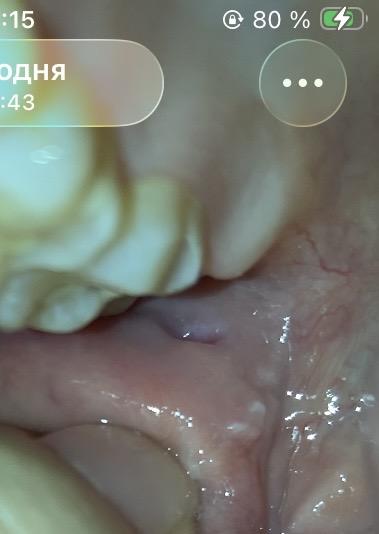

Мучают периодически жуткие боли. Думала, что зуб мудрости, но сейчас увидела белые шарики. Может ли это быть онкология?

Периодически в течении нескольких лет мучаюсь с болями по 2-3 недели.